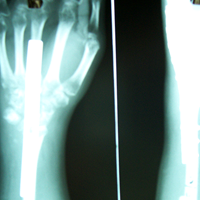

Case:1 GCT L/E Radius

Limb Reconstruction Doctor in Ahmedabad

Pre-Op

Rehablition Doctor In Ahmedabad

One and Half month follow up

Rehablition Best Doctor In India

One and Half year foll

2 years Follow-Up

Case:2 GCT-L/E Radius